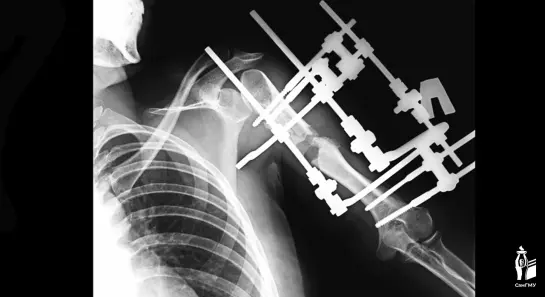

В Самарской области хирурги провели уникальную операцию. В клинике СамГМУ врачи удлинили руку девушки на 13 сантиметров.

- Удлинение верхней конечности на такую большую величину за одну операцию — смелое решение, мы понимали, что есть риски осложнений. Для удлинения на такую большую величину подходит метод Илизарова, при котором поэтапно выращивается своя собственная кость, - пояснил врач Никита Лихолатов.

Как пояснил медик, обычно такое растяжение у детей проводится на 1 мм в сутки. Костные фрагменты раздвигаются, между ними образуется мягкая костная мозоль, которая в дальнейшем перестраивается в кость. Но так как девочке было уже 17 лет, процесс растяжение проходил медленнее обычного - менее 1 мм в сутки, чтобы избежать повреждения мягких тканей.